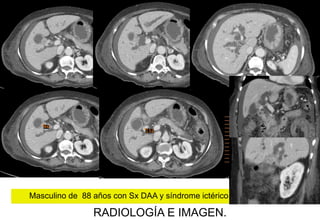

Masculino de 88 años con Sx DAA y síndrome ictérico.